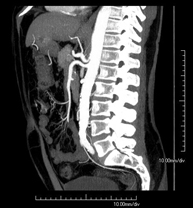

- Abdominal aorta CT angiography

A non-invasive diagnostic test that involves studying the abdominal aorta by obtaining high-definition anatomical images using CT (computed tomography) equipment and iodinated contrast. With the aid of workstations specialised for arterial studies, the image quality supports 2D and 3D reconstructions. It is indicated in patients with vascular disease (atherosclerosis), aortic aneurysms, abdominal pain of possible vascular origin, pre-surgical studies of lesions adjacent to the abdominal aorta as a vascular ‘map’, etc. Information obtained non-invasively is indispensable for patients requiring percutaneous or surgical processing. In patients who only require tracking of vascular lesions, this technique is the non-invasive technique of choice, together with MRI angiography.